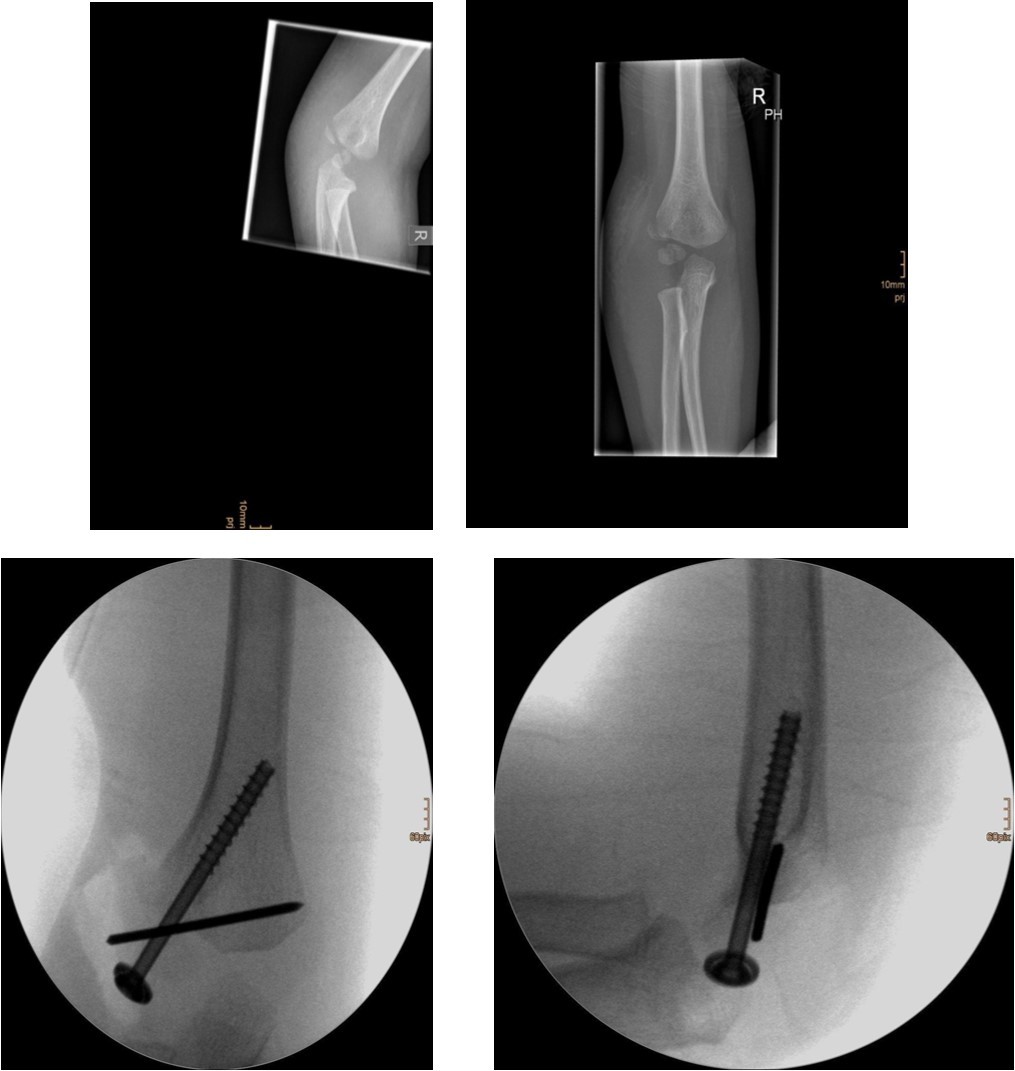

Figure 2.6 year old male patient with a dislocated right lateral condyle fracture which was treated by open reduction and osteosynthesis with a screw and a Kirschner wire (personal collection)

Non-displaced and stable fractures may be treated by cast immobilization with close follow-up, but fractures displaced >2 to 3 mm may indicate surgical fixation 7, 8. Surgical treatment can be done either by closed reduction and percutaneous osteosynthesis or open reduction and osteosynthesis. Figure 3.

Surgical fixation is either by screw, smooth K-wires or both. The K-wires can be buried under the skin or not.